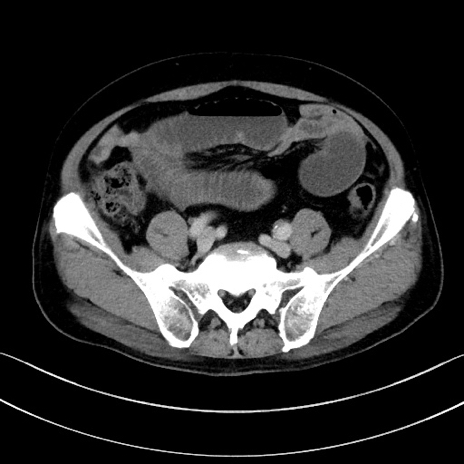

症例15(横断像)

【症例】70歳代男性

【主訴】腹痛

【現病歴】今朝から腹痛あり。全体的に痛い。特に左上の方。排ガスが今日はない。冷や汗が出る。

【既往歴】直腸癌術後

【身体所見】左側腹部〜上腹部に圧痛あり。腹膜刺激症状明らかなではない。軽度反跳痛。左下腹部に術後瘢痕あり。

【データ】WBC 7700、CRP 0.02